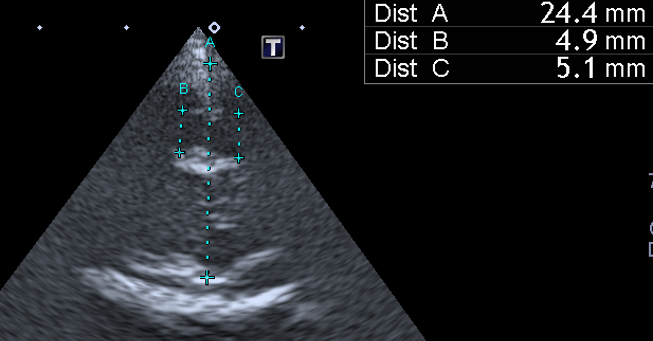

1. 초음파 (Ultrasonography) 진단 기준

초음파는 주로 대천문(Fontanelle)이 닫히지 않은 어린 고양이나, 측두골(Temporal bone)이 얇은 부위를 통해 검사합니다.

- 진단 기준 (측뇌실 높이):

- 정상 범위: 일반적으로 고양이의 측뇌실은 매우 좁아 초음파상에서 거의 보이지 않거나 높이가 2mm 미만인 것이 정상입니다.

- 뇌수두증 의심/진단: 측뇌실 높이가 2mm 이상으로 확장되었을 때 뇌수두증을 강력히 의심합니다. 일부 문헌에서는 3mm 이상을 확실한 병변으로 간주합니다.

- 초음파 영상에서 뇌실이 확장되어 뇌 실질(Brain parenchyma)이 얇아진 소견이 관찰됩니다.